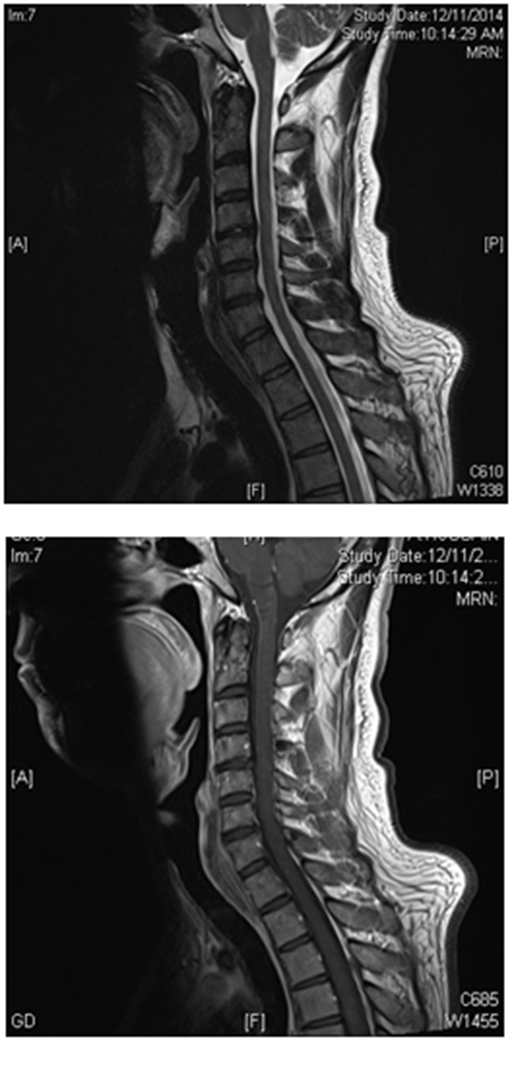

His blood cell count and blood film returned back to normal within 2 weeks of treatment initiation. Serum B12, homocysteine and MMA returned back to normal within 3 months. His motor strength, gait and balance showed subsequent marked steady improvement at 1-month, 3-months and 6-months follow- up visits. MRI of the cervical spine with contrast was repeated after 3 months of treatment and showed complete resolution of the cervical lesion (Figure 5).

Figure 5 Follow up MRI Cervical spine (sagittal view) with and without contrast showing complete resolution of the cervical myelopathy.

MRI is an important and sensitive tool in diagnosis of SCD; on sagittal images, a vertical segment can be seen at the posterior aspect of the spinal cord and B12 deficiency should be suspected in cases with longitudinally extensive transverse myelitis (LETM). On axial images, bilateral paired areas of T2 hyperintensity are seen as an “inverted V” or “inverted rabbit ears” (Figure 4) in the dorsal columns. Lateral column involvement is seen in severe cases. Contrast enhancement is uncommon. Signal abnormalities are usually reversed after treatment within a few months. MRI of the brain may show abnormal signal intensity on T2-weighted images in the cerebral white matter.8